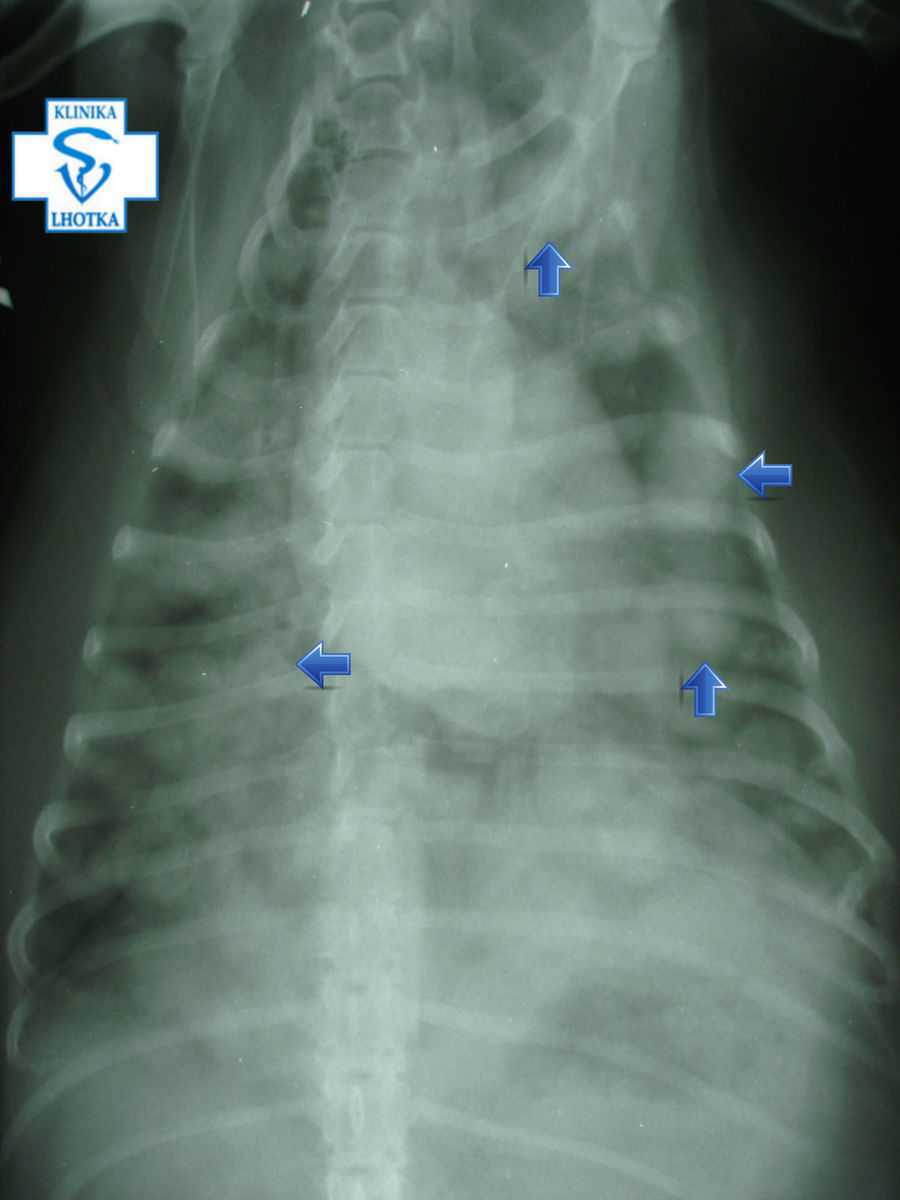

Tato vyšetření nám bohužel odhalila četné metastáze v plicích i na orgánech v dutině břišní.

Na rentgenogramech jsou šipkami označeny některé z mnohočetných kulovitých metastáz v plicích způsobujících dechové potíže.